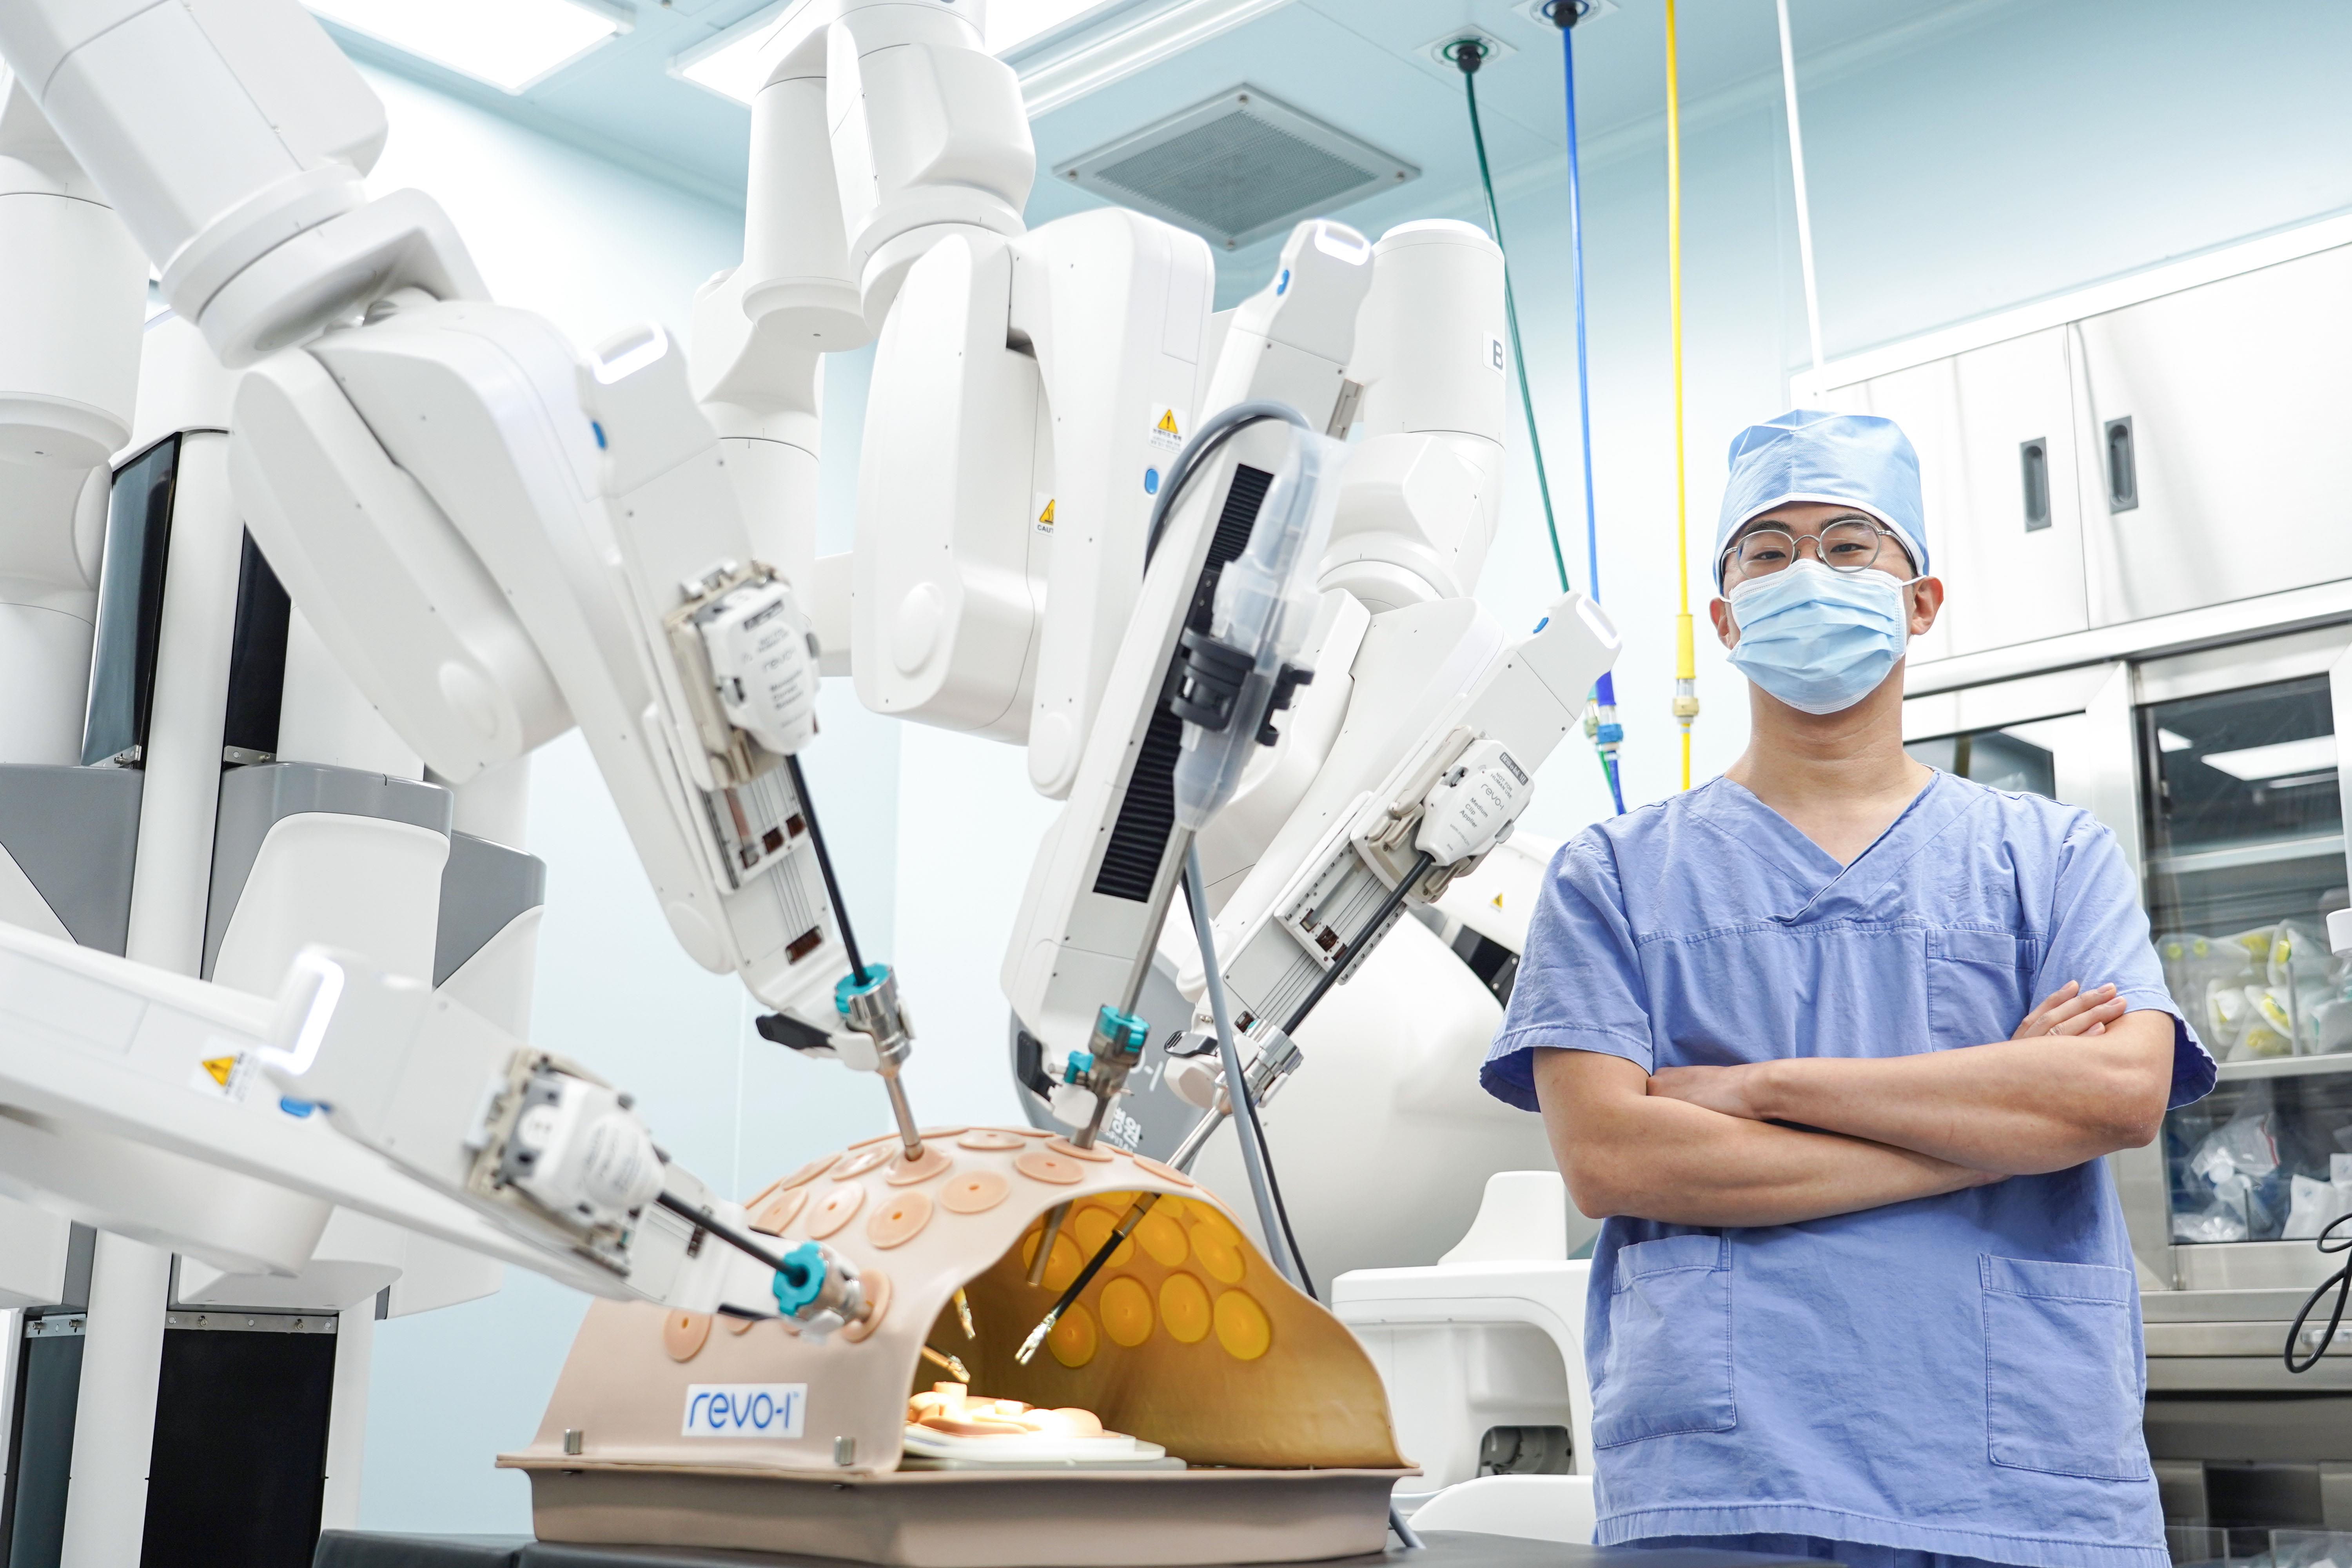

췌장머리암으로 인한 췌두부십이지장절제술은 췌장과 십이지장, 담관, 담낭을 광범위하게 절제하고 이를 소장과 연결하는 등 과정이 복잡하고 정교한 문합기술이 필요한 수술이다 보니 췌장암 수술은 대부분 배를 가르는 개복수술이 표준 치료였으며, 현재까지도 가장 많이 하는 수술방법입니다.

하지만, 개복수술은 긴 절개로 인해 수술 후 통증이 심해 환자분의 회복 속도가 더뎌 수술 후 일상으로의 복귀가 느린 특징이 있어, 최근에는 수술 기법의 발달로 복강경 수술과 로봇수술을 어려운 수술에도 접목을 시키려는 시도가 있는데, 어려운 췌장절제술의 경우, 복강경 또는 로봇수술을 시행하고 있으며, 전세계적으로도 점점 증가하고 있는 추세입니다.

특히, 인체 깊숙히 위치한 췌장, 그리고 그 주변의 복잡한 해부학적 구조, 절제 후 어렵고 정교한 문합을 시행해야 하는 췌장절제술에 절개를 최소화하고 확대된 시야, 안정된 움직임을 가능하게 하는 로봇수술은 개복 수술에 비해 수술 후 환자분의 통증을 줄여주고 합병증 발생률을 낮춰 회복을 빠르게 하고 조기에 사회로 복귀시키는 방법이라 할 수 있습니다.

여러 장기를 광범위하게 절제하므로 수술의 안정성 확보와 합병증 최소화는 환자의 생명과 직결이 되기 때문에 로봇수술을 시행하게 되는데, 명주병원에서 시행하고 있는 로봇수술 치료의 경우, 확대된 시야 속에서 최소한으로 절개하여 정교한 수술이 가능하고, 출혈이 적고 통증이 적어 개복수술에 비해 회복이 빠릅니다.

복부에 5~6개 정도의 약 2cm정도 구멍을 뚫은 뒤에 로봇팔을 꽂아 시행하는 로봇수술은 적은 흉터 뿐 아니라 수술 후 통증이 적고 회복이 빠르다는 장점이 있어 환자 만족도가 높은 편입니다.

또한, 넓은 시야 확보가 가능하고, 안정된 로봇팔을 이용하여 수술하다보니 정교하고 안전한 수술을 시행할 수가 있습니다.